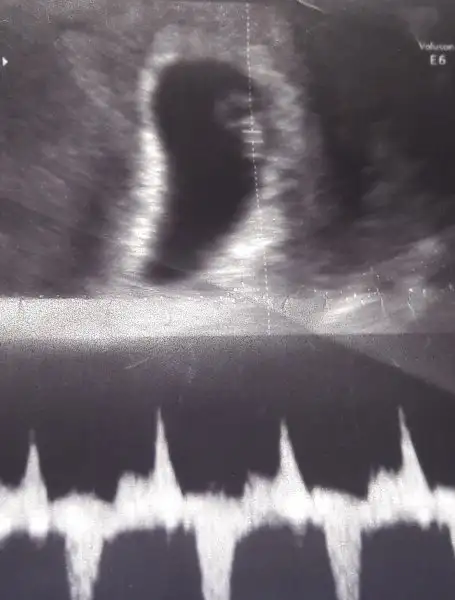

Çok sağol canım sürpriz yumurtamız bu...oy maşallah. üçüncü mü bu. Allah yardımcınız olsun.

Canım bende aynı durumdayım yaş 35 üçüncü gebelik ve bende yatın sonucu almaya gideceğim sende dua et olur mu aslında ense kalınlığı normal dedi doktor ilk iki gebeliğimde yaptırmamıştım bunda doktora yaptırmak istemiyorum diyemedim dediğin gibi yaşta olunca bakalım yatın saat 10 da hastanedeyimYarın 2li testim var, dua edin anneler.

Yüksek riskli gebelik benimkisi..

Yaş 36...Insan korkuyor.